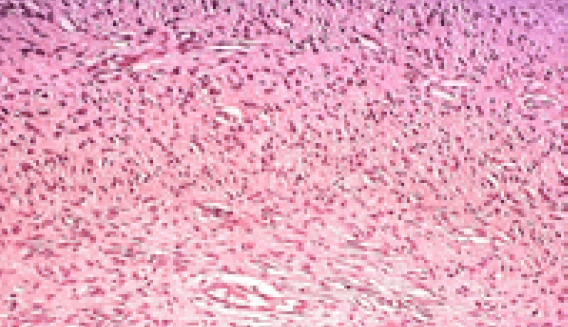

Se realizaron biopsias excisionales de las lesiones y envío para procesado y estudio histopatológico, reportando lesión de origen nervioso benigna revestida por un epitelio plano estratificado queratinizado de espesor variable con apariencia normal en corte con coloración de hematoxilina y eosina (H-E) (Fig.5), con presencia de células poligonales y otras fusiformes compatibles con células nerviosas y una proliferación desorganizada de fibras colágenas, fibroblastos ahusados, mastocitos, adipocitos y vasos sanguíneos tapizados por endotelio. (Fig. 6)

Figura 5. lesión a bajo aumento. Coloración de H-E.

Figura 6. lesión a mayor aumento. Coloración de H-E. Figuras 5 y 6. Estudio histopatológico.